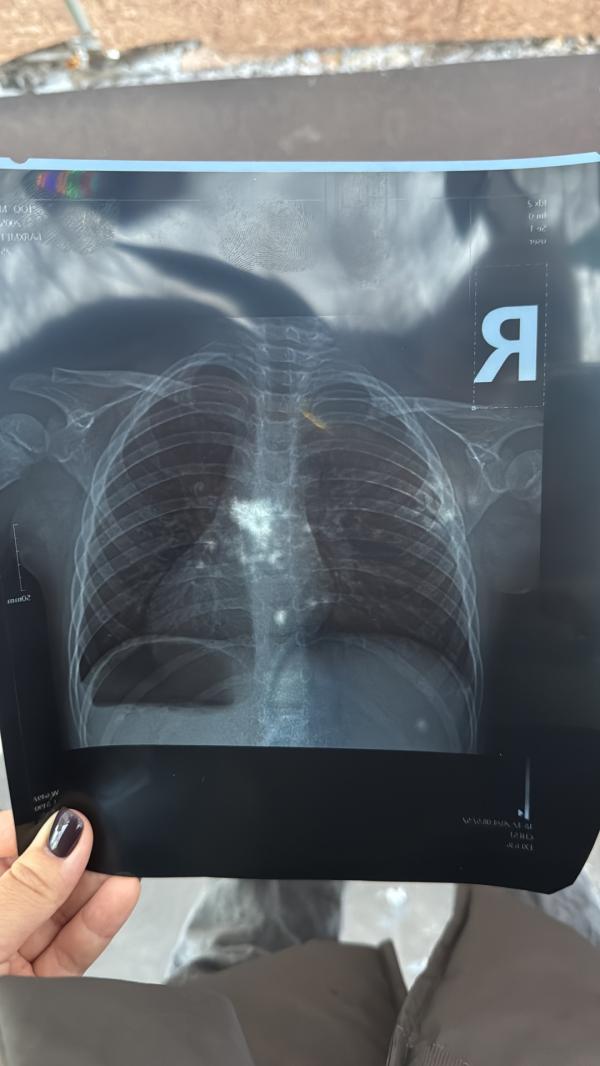

Мамы, доброе утро! Я одна здесь вижу пневмонию?

Тут что то по мощнее даже возможно,нужен пульмонолог ,как по мне пневмония очевидна